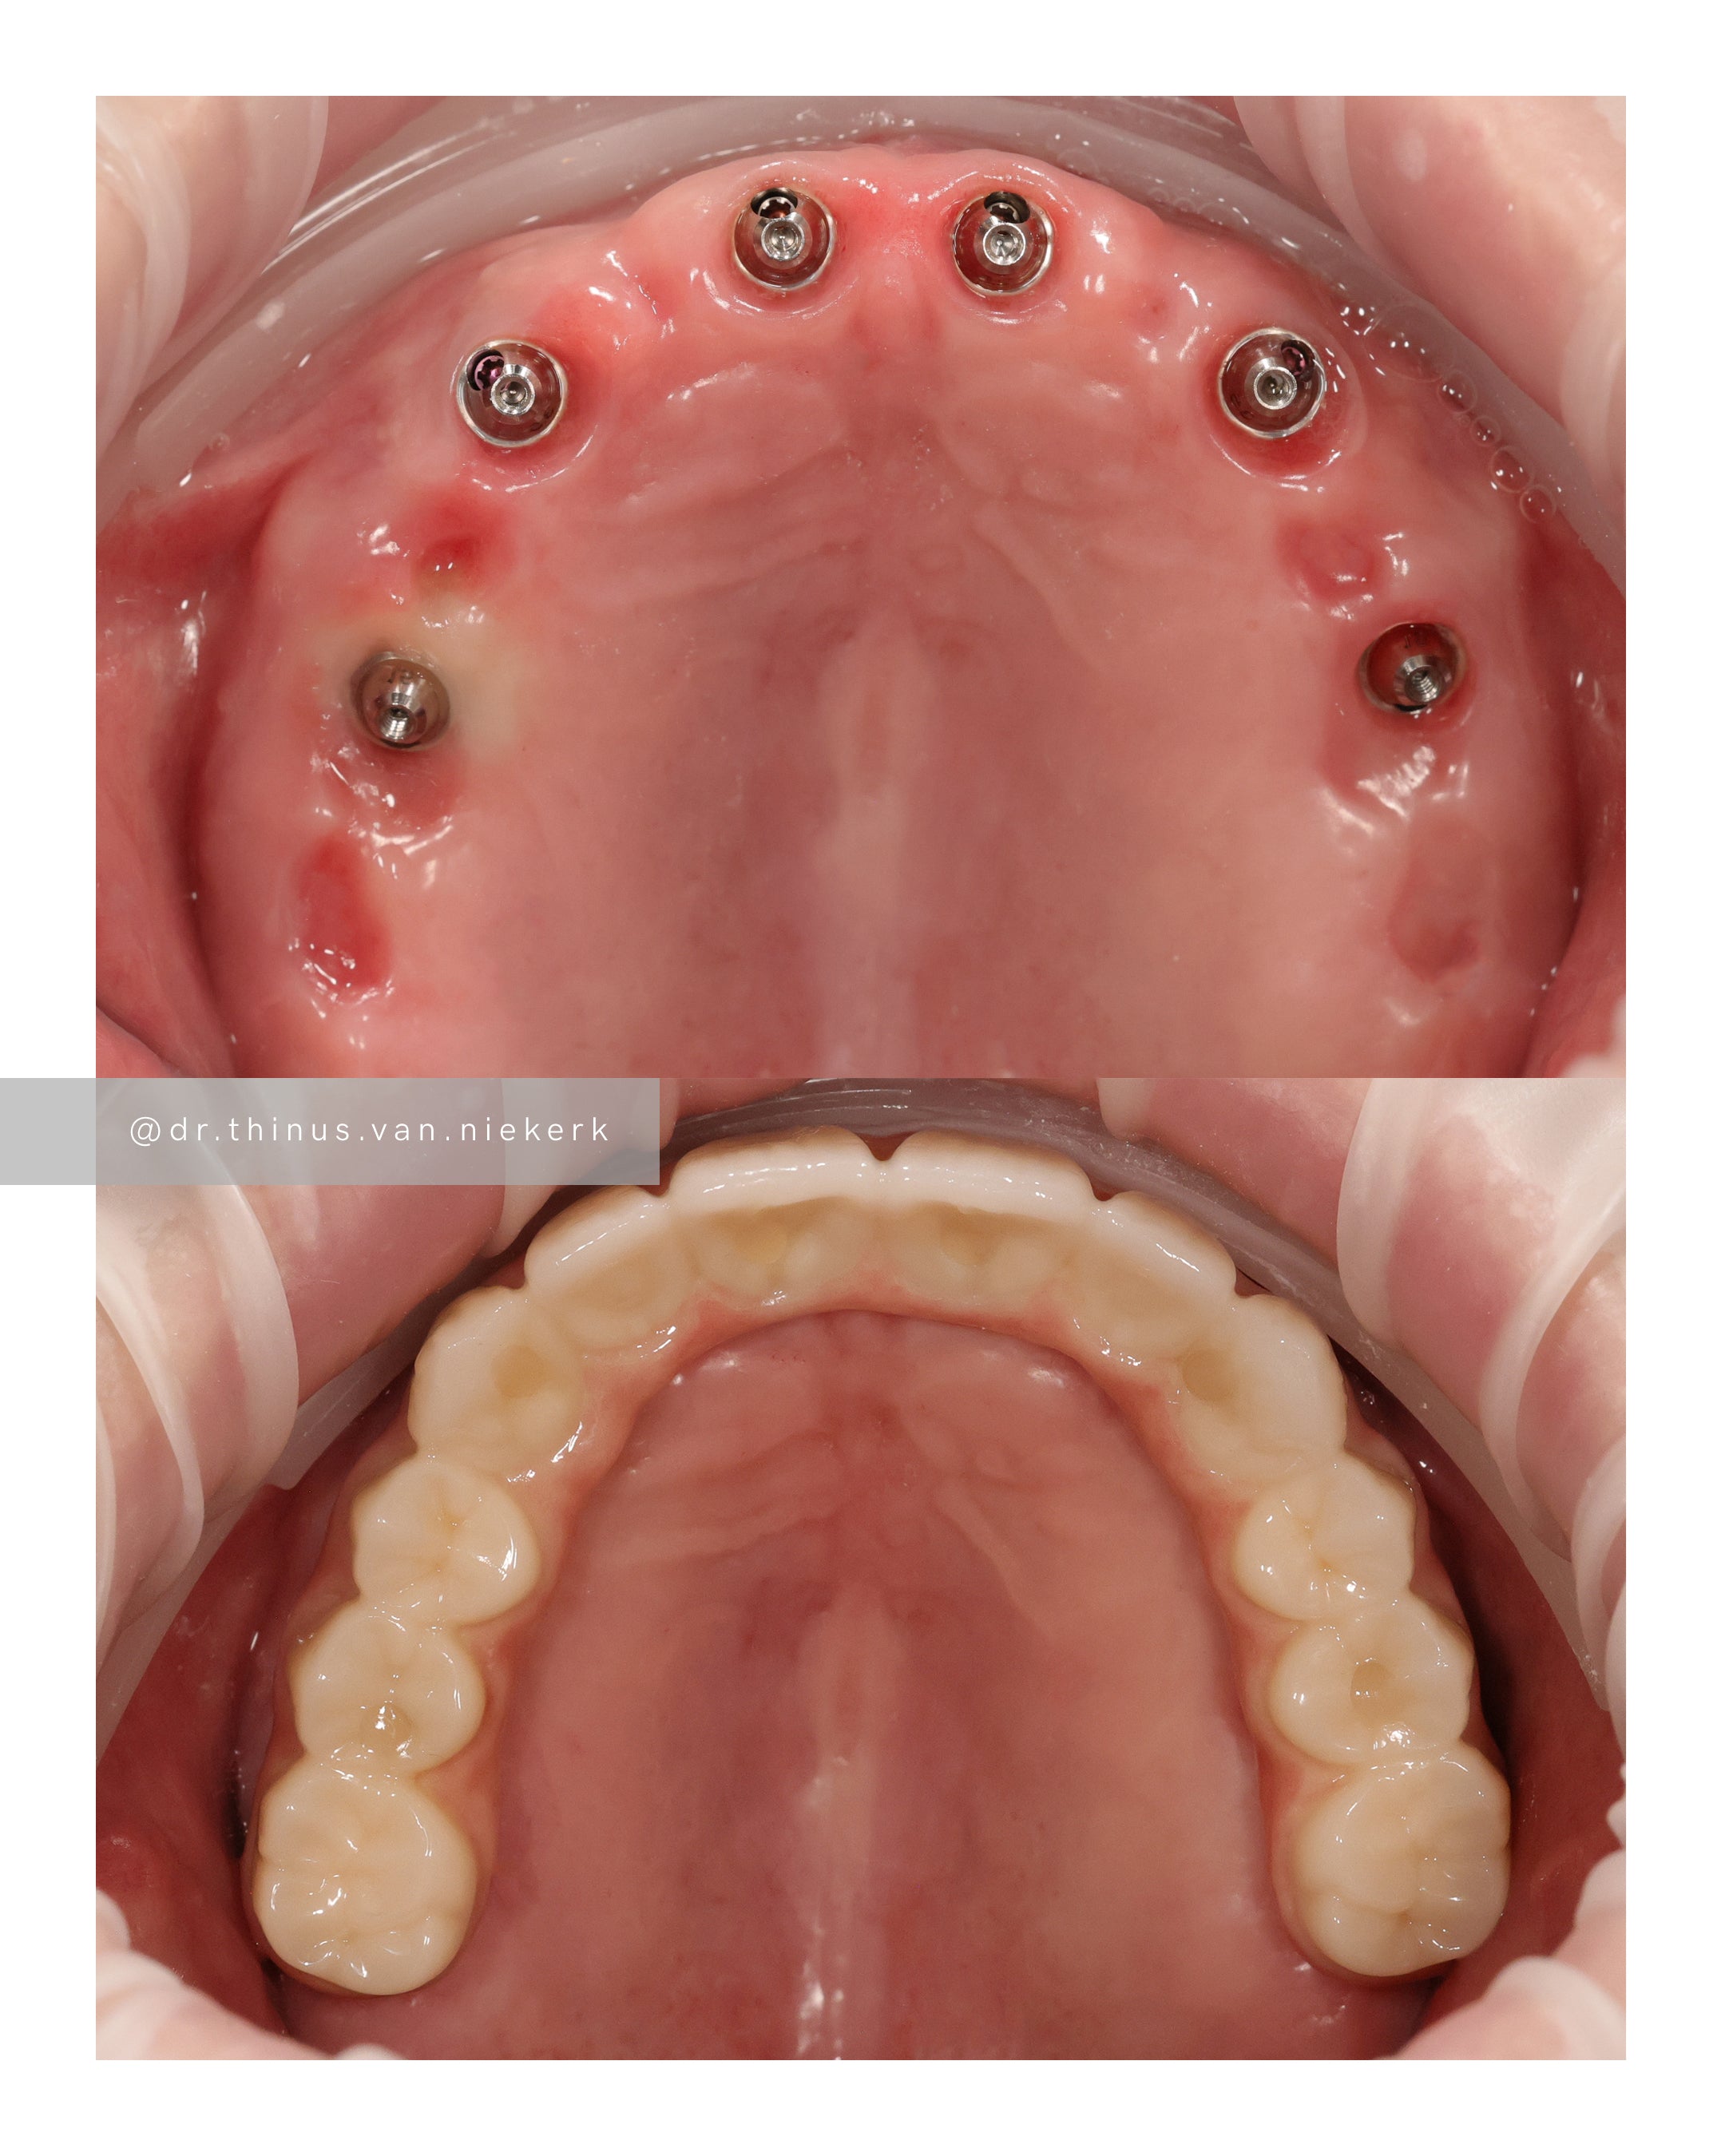

Our patient endured a long history of oral disease and associated infections. Our aim was to remove all elements of infection and disease and to restore function as quickly as possible. Six fully-guided implants were placed and immediately restored with implant-supported prosthesis in both the upper and lower jaws respectively. These were then converted to final zirconia framework prosthesis as healing and tissue remodeling allowed. The complete timeline for a treatment such as this varies from 6-24 months.

COMMENTS

This was a landmark case for our clinic – being the first fully digitally-planned upper and lower rehabilitation. This case demonstrated the power and effectiveness of digital implant-surgery planning and CAD design software. No adjustments were needed at the placement of the final lower prosthesis.